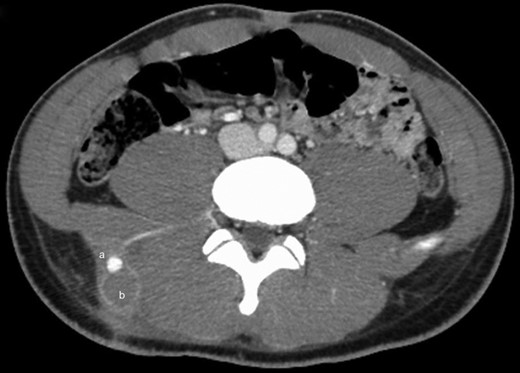

Examination on admission revealed an actively bleeding 2-cm wide stab wound in the right lumbar paraspinal region. A contrast-enhanced CT of the pelvis showed an enhancing lesion consistent with a pseudoaneurysm extending from a branch of a right lumbar artery (Figs 1 and 2). The patient was transferred to the interventional radiology suite where angiography confirmed the diagnosis (Fig. 3). The pseudoaneurysm was then successfully embolized using platinum microcoils (Fig. 4), which were positioned in the lumbar artery, proximal and distal to the origin of the pseudoaneurysm. The patient tolerated the procedure well and was discharged the following day without any further complication.

Contrast-enhanced CT scan of the lower abdomen and pelvis showing a single lobe of a presumed, bilobed pseudoaneurysm (a) as well as a 3.5 × 5.5 × 6 cm rim-enhancing, lobular collection of the superior right gluteal subcutaneous tissues, just superior to the right iliac crest and lateral to the paraspinal musculature, consistent with a hematoma (b).